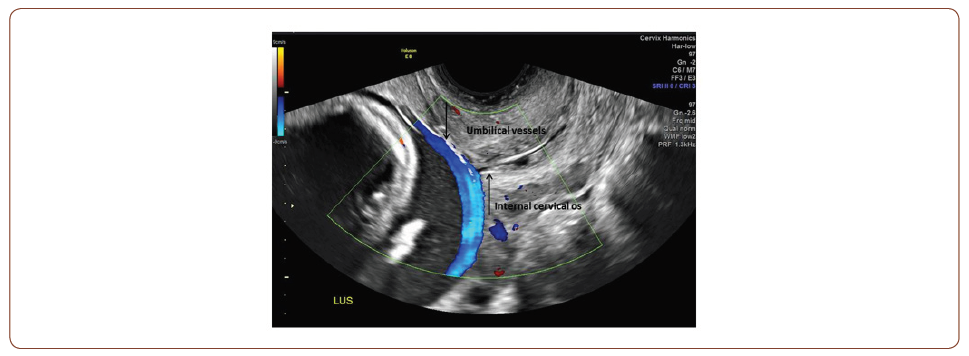

Umbilical Vessels Traversing Cervical Os: Vasa Previa

This image demonstrates the ultrasound diagnosis of vasa previa in a 37-year-old primigravid woman who presented for a routine detailed fetal anatomic survey at 21 weeks gestation. Obstetric management consisted of pelvic rest, serial fetal growth scans starting in the late second trimester, and antenatal corticosteroids for fetal lung maturity at 33 weeks. Due to the risk of rapid fetal exsanguination with rupture of the vasa previa, the patient was admitted to the antepartum service at 35 weeks for observation. The patient fortunately experienced an uncomplicated antepartum course with the delivery of a healthy infant via nonemergent cesarean section at 36w3d. The placental pathology was consistent with the prenatal diagnosis of a velamentous cord insertion leading to the vasa previa.